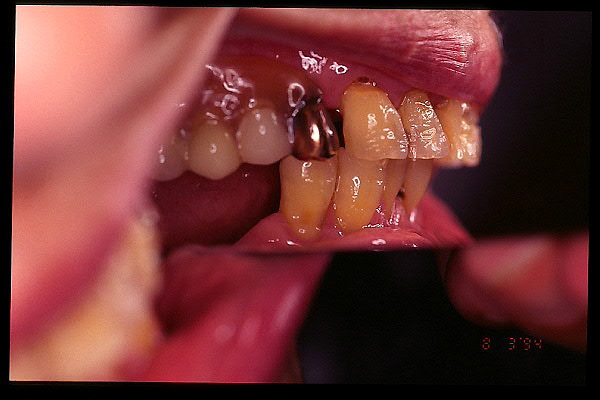

CM Extrusión de molar superior y premolares inferiores por falta de antagonista